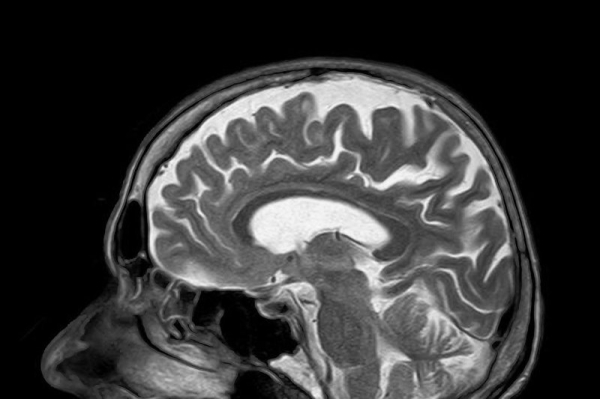

The drug announcement comes on the heels of news that scientists are using a type of MRI to help determine who might develop treatment-resistant schizophrenia.

The scan — called a neuromelanin-sensitive MRI — focuses on a brain pigment called neuromelanin, which can provide evidence of healthy dopamine function and help predict whether patients will respond to treatment.